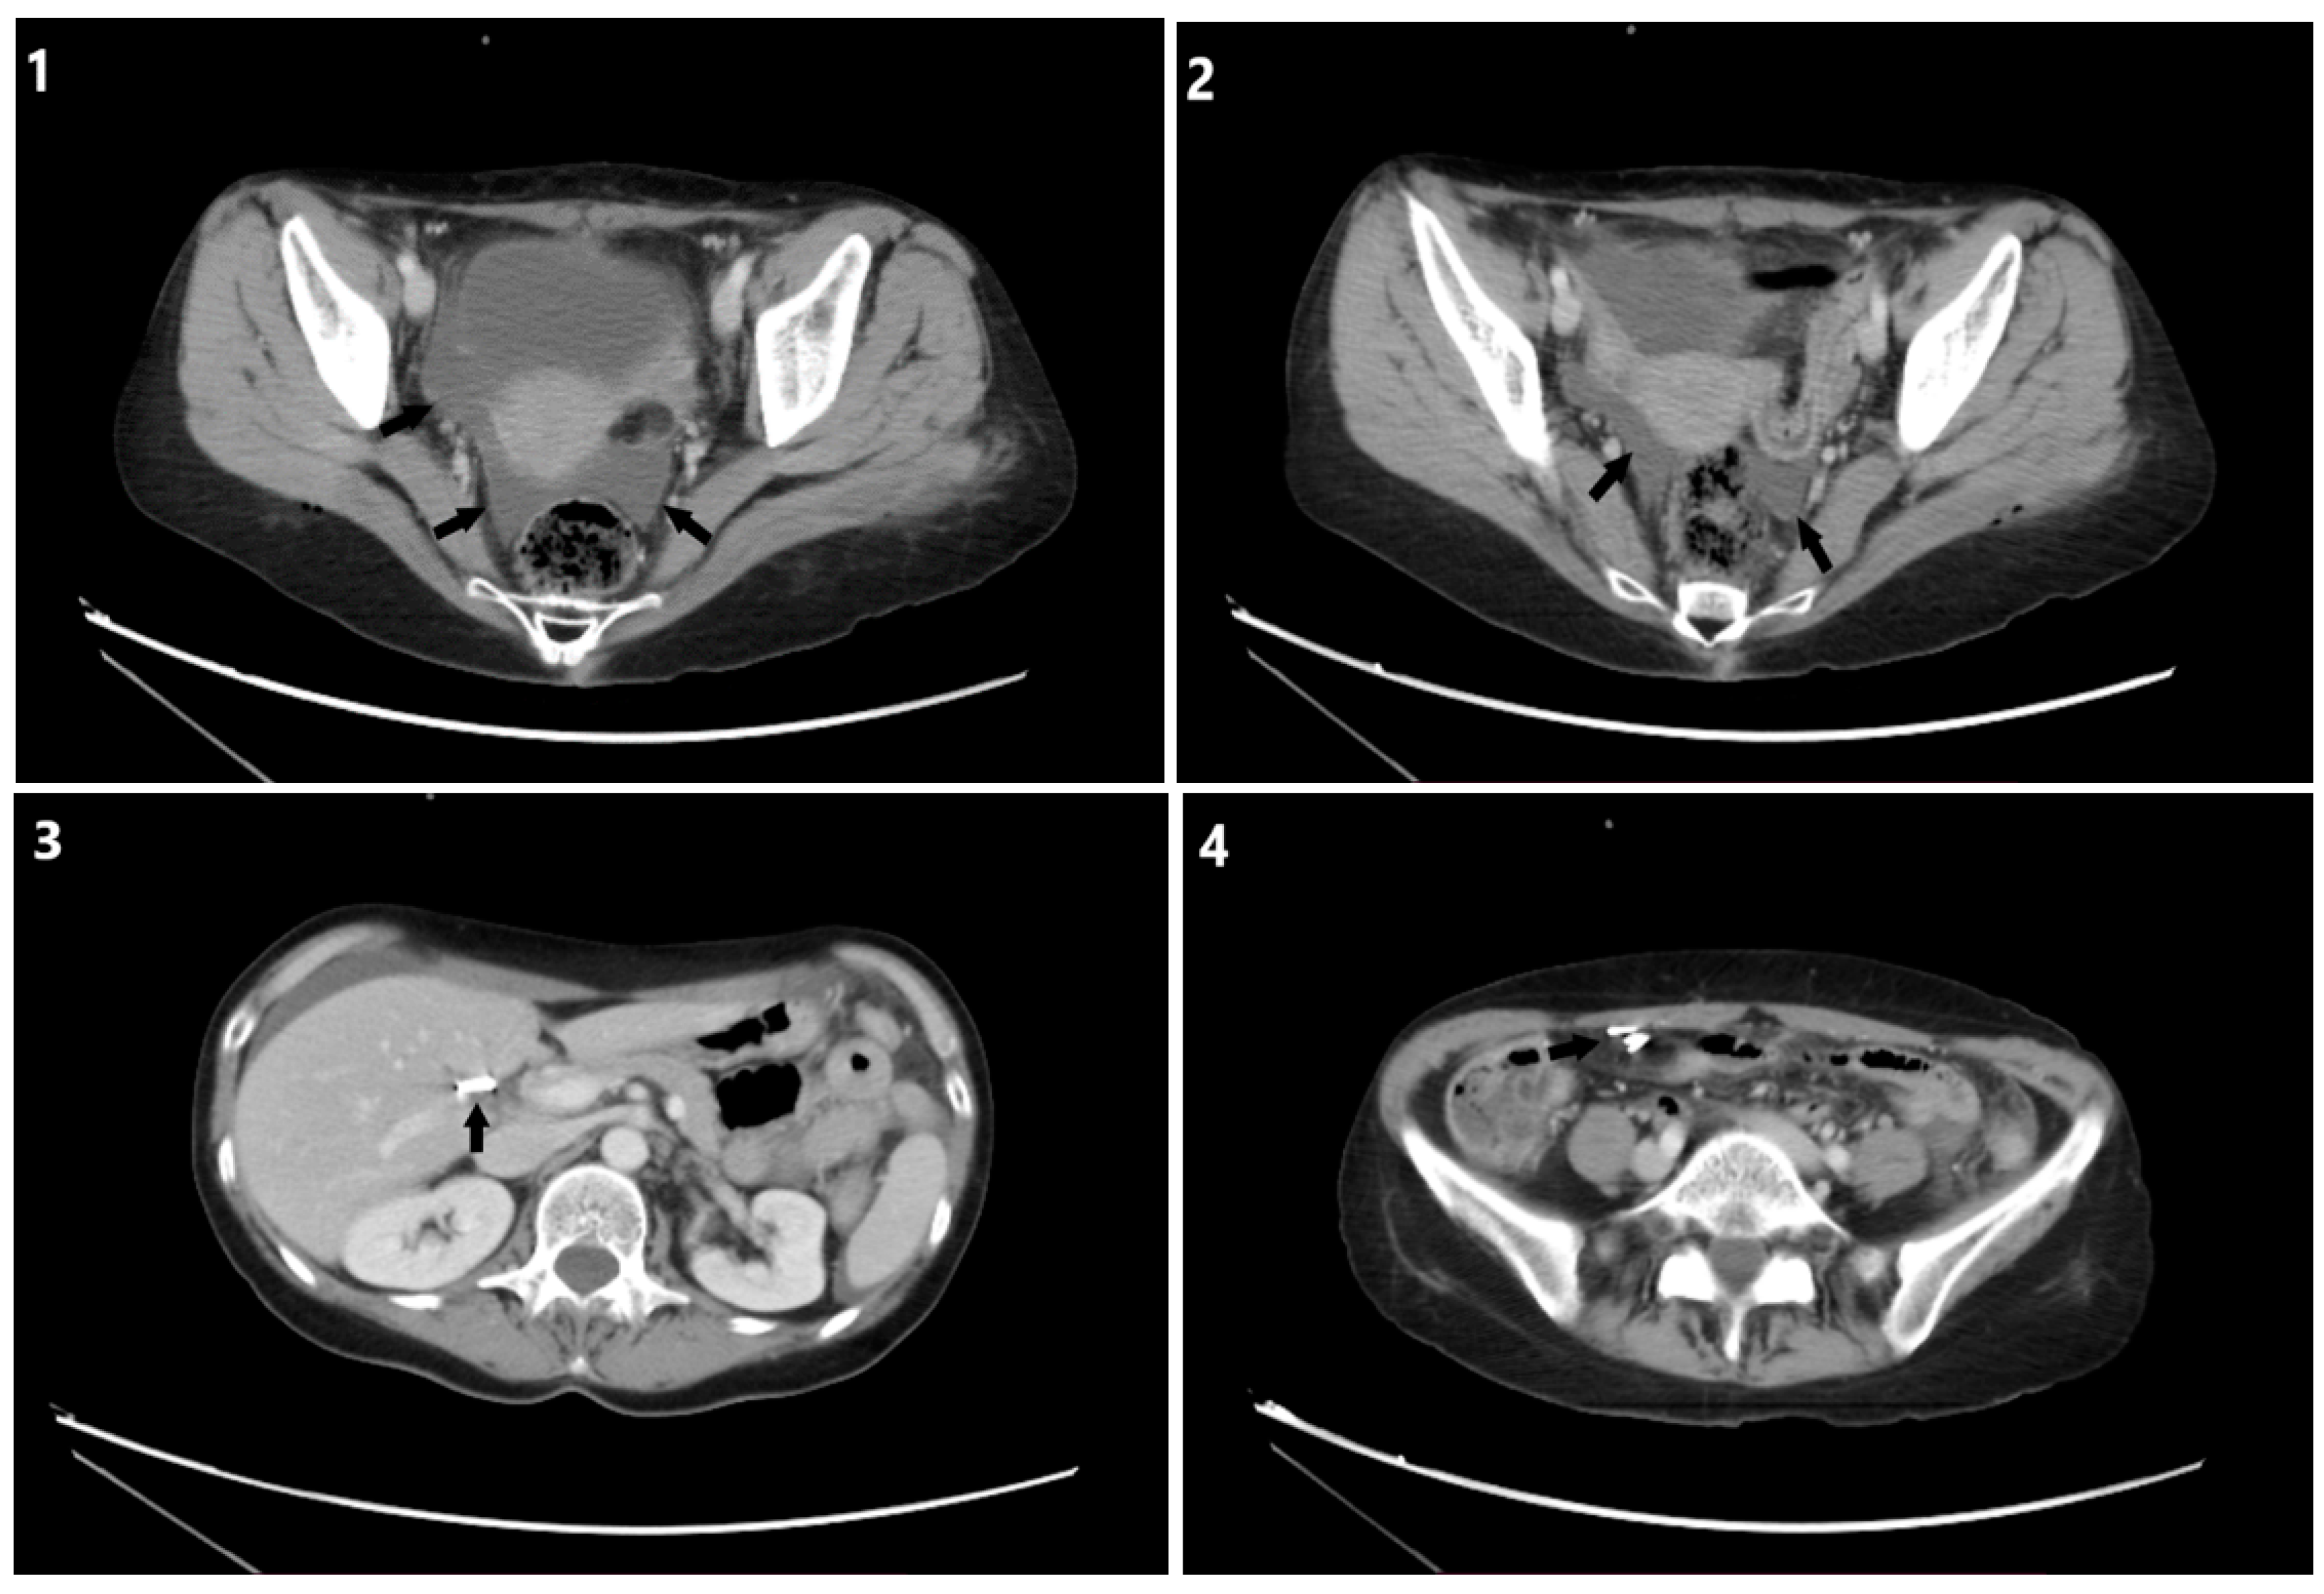

JPM Free FullText Uroperitoneum as a Complication of Laparoscopic

JPM Free FullText Uroperitoneum as a Complication of Laparoscopic Laparoscopic Wound Leaking If you notice any of the. Incision and surgical wound care are instructions that you follow to prevent infections and help your body heal. A seroma, one of the most common potential complications after surgery, refers to the accumulation of uninfected and clear (i.e., serous) fluid under the skin. Seroma formation may occur due to fluid leaking out of the. Laparoscopic Wound Leaking.